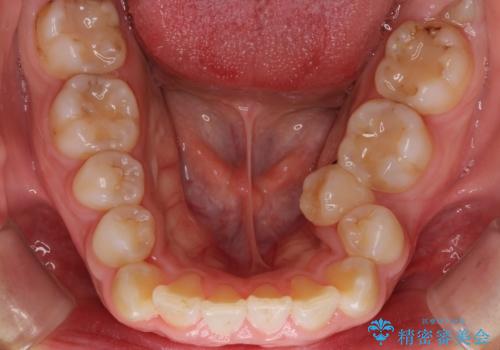

- 歯並びがガタガタなのと、口が閉じずらいのを主訴に来院されました。

上下左右の歯を1本ずつ、合計4本抜歯して、ワイヤー矯正を行うこととなりました。

右上の歯は、歯並び的には前から4番目の歯を抜歯したかったのですが、5番目の歯がすでに治療してある歯でしたのでこちらの歯を抜歯しました。

これにより少し治療期間が延びてしまいましたが、健康な歯を残すことができました。